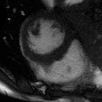

Supervised Deep-Learning (DL)-based reconstruction algorithms have shown state-of-the-art results for highly-undersampled dynamic Magnetic Resonance Imaging (MRI) reconstruction. However, the requirement of excessive high-quality ground-truth data hinders their applications due to the generalization problem. Recently, Implicit Neural Representation (INR) has appeared as a powerful DL-based tool for solving the inverse problem by characterizing the attributes of a signal as a continuous function of corresponding coordinates in an unsupervised manner. In this work, we proposed an INR-based method to improve dynamic MRI reconstruction from highly undersampled k-space data, which only takes spatiotemporal coordinates as inputs. Specifically, the proposed INR represents the dynamic MRI images as an implicit function and encodes them into neural networks. The weights of the network are learned from sparsely-acquired (k, t)-space data itself only, without external training datasets or prior images. Benefiting from the strong implicit continuity regularization of INR together with explicit regularization for low-rankness and sparsity, our proposed method outperforms the compared scan-specific methods at various acceleration factors. E.g., experiments on retrospective cardiac cine datasets show an improvement of 5.5 ~ 7.1 dB in PSNR for extremely high accelerations (up to 41.6-fold). The high-quality and inner continuity of the images provided by INR has great potential to further improve the spatiotemporal resolution of dynamic MRI, without the need of any training data.

翻译:在这项工作中,我们建议了一种基于IRI的方法,用这种方法来改进动态磁共振感应成像(MRI)重建,而该方法只是以高度低劣的 k-空间数据为基础,而该数据仅以磁共振坐标作为投入。具体地说,拟议的IRI将动态MRI图像作为一种隐含功能来表示,并将其编码到神经网络中。网络的权重仅从稀有的(k, t)空间数据本身中学习,而没有外部培训数据集或先前的图像。 利用基于IRI的强有力隐含性稳定化,同时不以清晰的动态和时空坐标坐标坐标坐标坐标作为投入。 拟议的IRIR将动态MRI图像作为一种隐含功能,将其编码到神经网络中。网络的权重仅从淡化的(k, t)空间数据本身学习,而没有外部培训数据集或先前的图像。